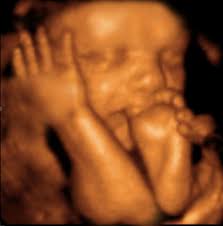

Male 16 Week Ultrasound 3d

Fetal Ultrasound Image Gallery Fetal Pictures Of Ultrasound